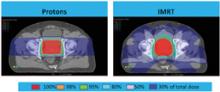

Tune in to ITN’s latest “One on One” video series with Michael Butkus, PhD, for insights into proton therapy advancements. Butkus is the co-medical director and head of proton physics at the Dwoskin Proton Center at the Sylvester Comprehensive Cancer Center, part of the University of Miami/UHealth Medical System. A board member of the National Association of Proton Therapy (NAPT), Butkus spoke with ITN’s managing editor to discuss how physicists, physicians and vendors are collaborating to expand availability of proton therapy and improve the health of patients being treated.